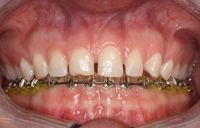

Voor de behandeling

Gebitsslijtage voornamelijk door knarsen. Aan de binnenkant zijn de tanden erg dun geworden en daardoor ook afgebroken. Door de diepe beet zijn de kiezen in onderkaak helemaal afgebroken.

Na de behandeling

De zes voortanden en twee kleine kiezen in de bovenkaak zijn opgebouwd met composiet. Hierdoor zijn ze verlengd en volledig ingepakt met composiet, zodat ze niet meer zo snel kunnen breken.

De afgebroken kies in de onderkaak is verwijderd en in het hiaat zijn twee implantaten geplaatst met kronen.

Uiteindelijk heeft meneer ook een beschermende nightguard gekregen om ervoor te zorgen dat het knarsen geen schade kan geven aan zijn gebit.